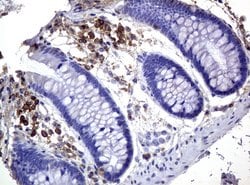

CD3 epsilon is part of the CD3 subunit complex which is crucial in transducing antigen-recognition signals into the cytoplasm of T cells and in regulating the cell surface expression of the TCR complex. T cell activation through the antigen receptor (TCR) involves the cytoplasmic tails of the CD3 subunits CD3 gamma, CD3 delta, CD3 epsilon and CD3 zeta. These CD3 subunits are structurally related members of the immunoglobulins super family encoded by closely linked genes on human chromosome 11. The CD3 components have long cytoplasmic tails that associate with cytoplasmic signal transduction molecules and this association is mediated at least in part by a double tyrosine-based motif present in a single copy in the CD3 subunits. CD3 may play a role in TCR-induced growth arrest, cell survival and proliferation. The CD3 antigen is present on 68-82% of normal peripheral blood lymphocytes, 65-85% of thymocytes and Purkinje cells in the cerebellum. It is never expressed on B or NK cells. Decreased percentages of T lymphocytes may be observed in some autoimmune diseases. The genes encoding the CD3 epsilon, gamma and delta polypeptides are located on chromosome 11. Defects in this gene are associated with T cell immunodeficiency and has been linked to Type 1 Diabetes deficiency in women.Specifications

| Immunocytochemistry, Immunofluorescence, Immunohistochemistry (Paraffin) | |